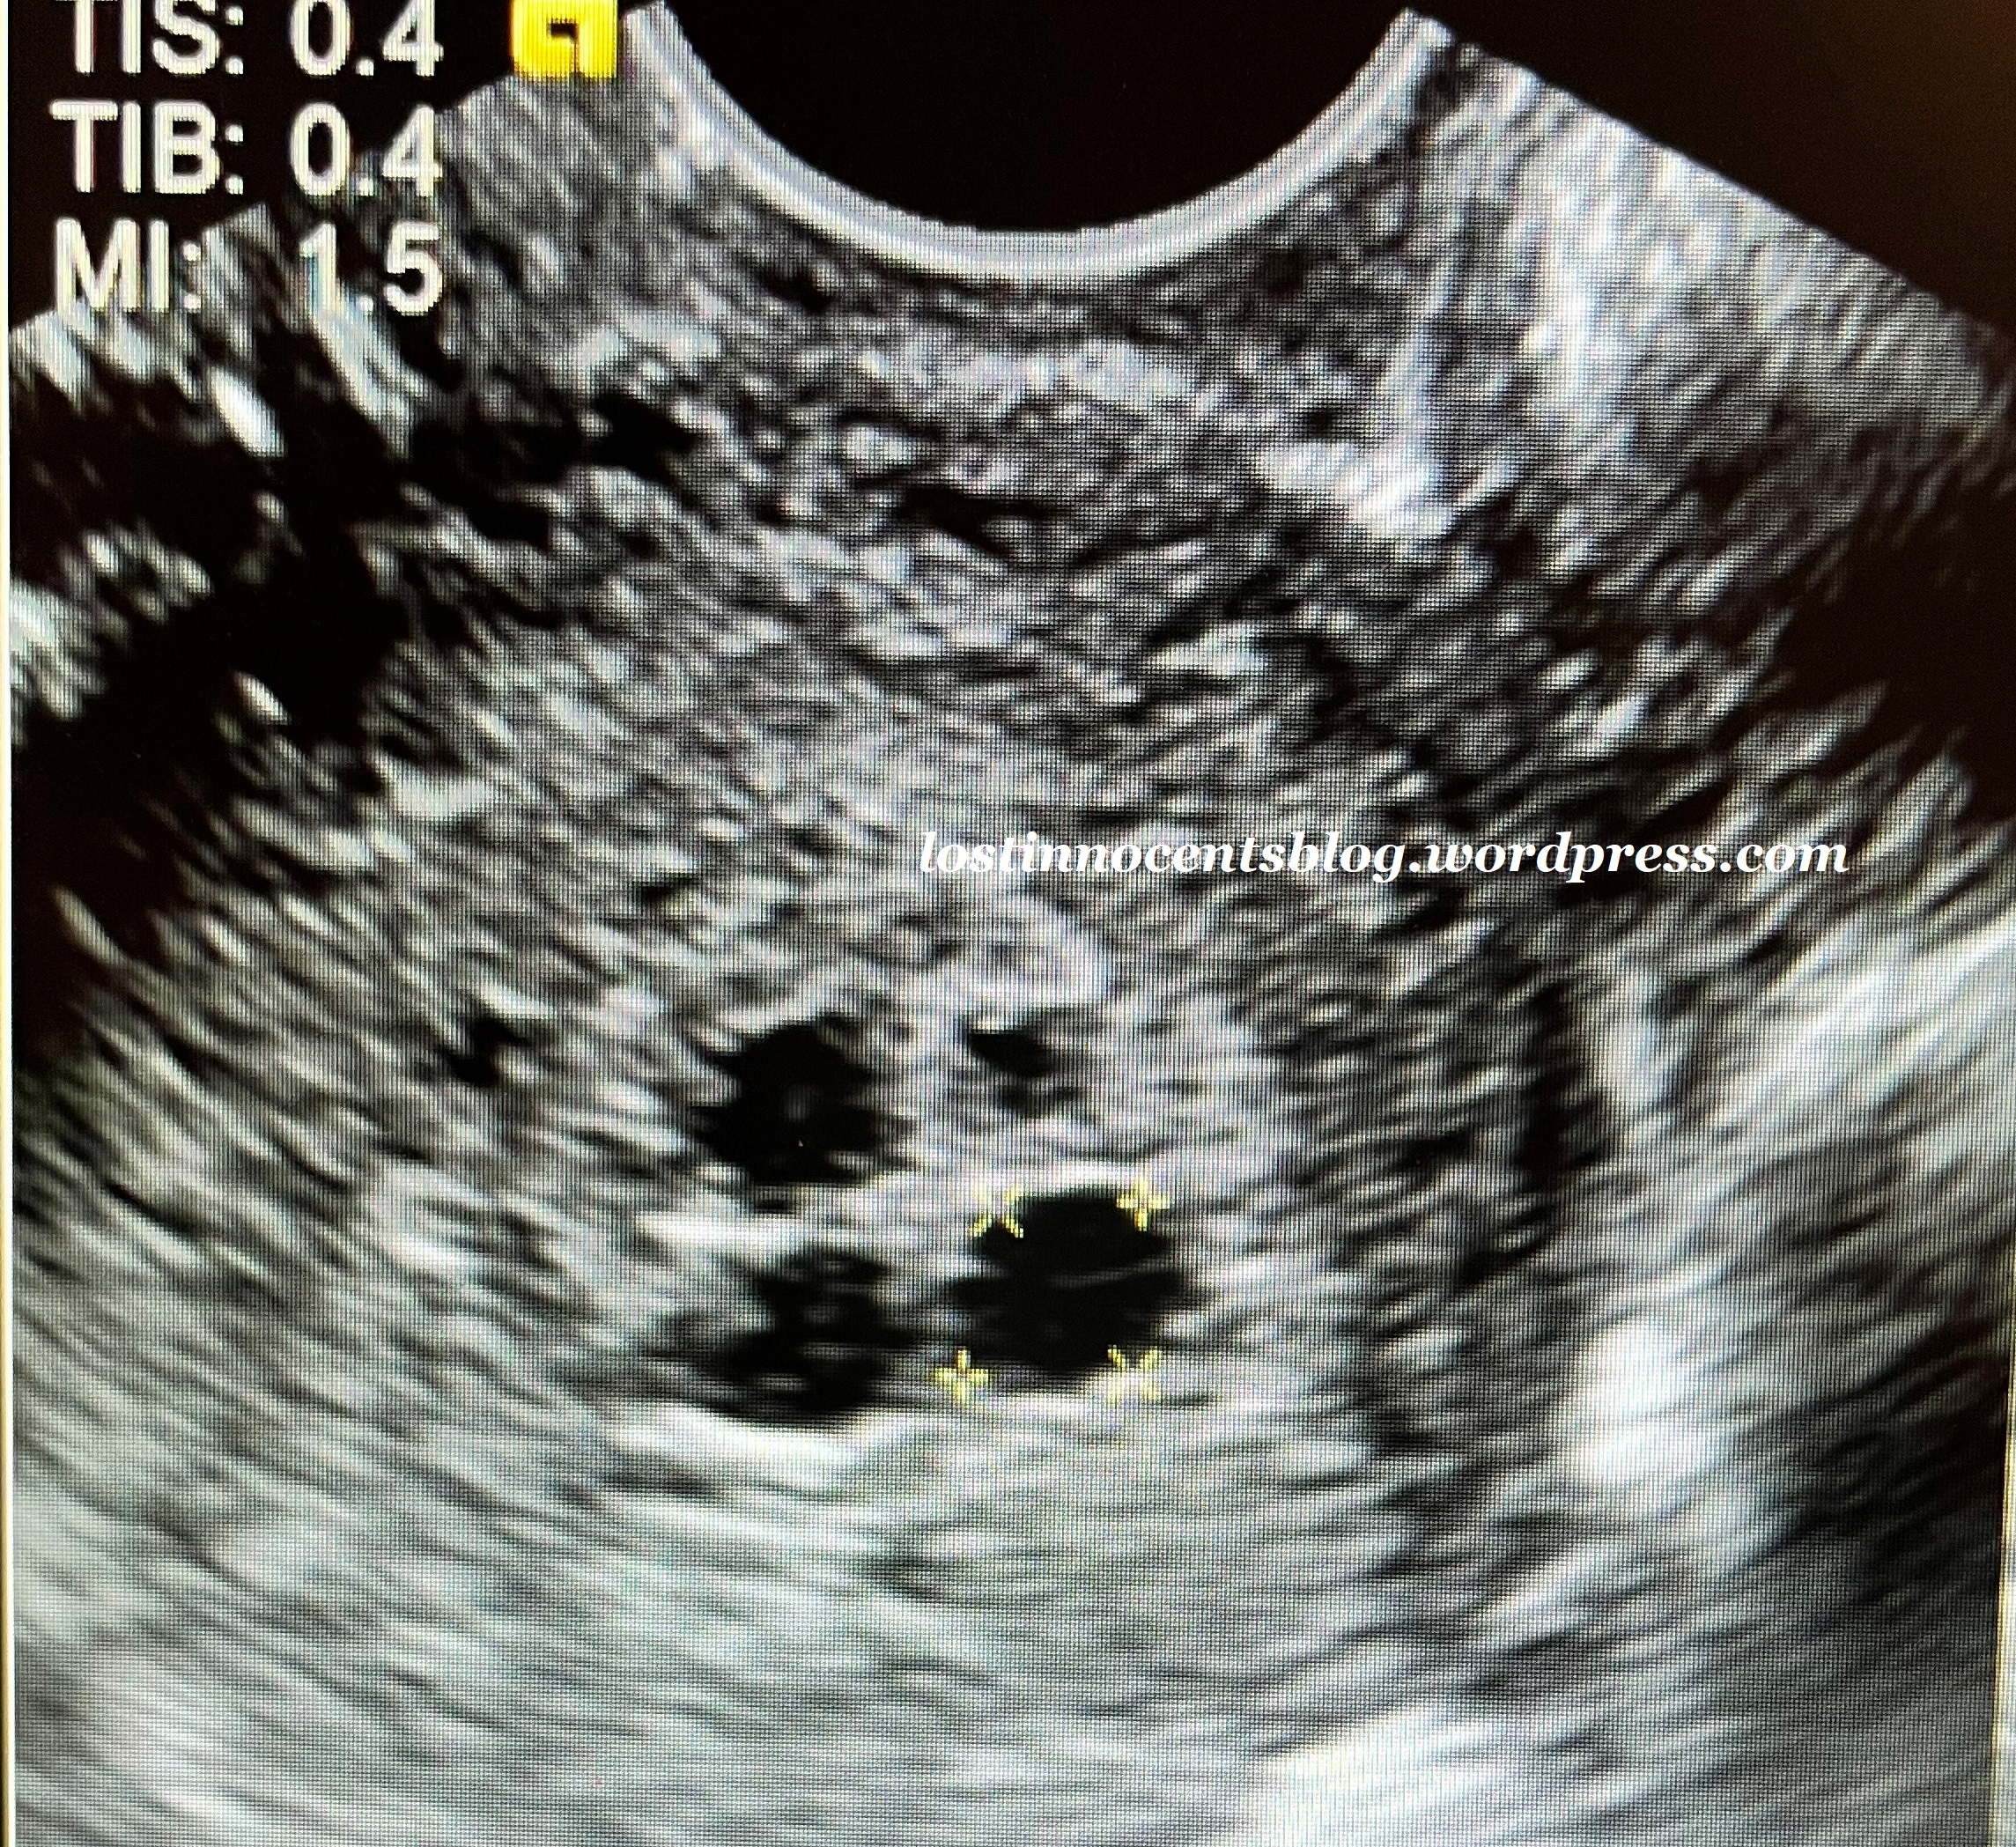

Elexus’s baby, Adam Scott Terry Jr. (measuring 4 weeks, ultrasound done at 4 weeks, 4 days)

Stephanie’s baby, Rose, approximately 4 weeks, 5 days